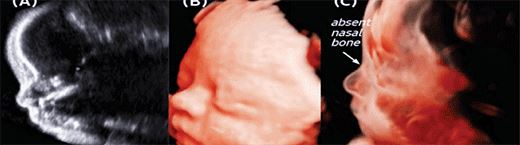

胎兒顏面部畸形評估:CrystalVue可以清楚地看到胎兒鼻骨缺失的情況(白色箭頭)。